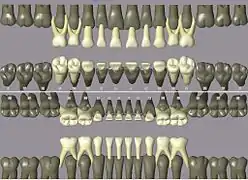

Codes, names, and usual number of roots: (see chart of teeth at Universal Numbering System)

- 11 21 51 61 maxillary central incisor 1

- 41 31 81 71 mandibular central incisor 1

- 12 22 52 62 maxillary lateral incisor 1

- 42 32 82 72 mandibular lateral incisor 1

- 13 23 53 63 maxillary canine 1

- 43 33 83 73 mandibular canine 1

- 14 24 maxillary first premolar 2

- 44 34 mandibular first premolar 1

- 15 25 maxillary second premolar 1

- 45 35 mandibular second premolar 1

- 16 26 54 64 maxillary first molar 3

- 46 36 84 74 mandibular first molar 2

- 17 27 55 65 maxillary second molar 3

- 47 37 85 75 mandibular second molar 2

- 18 28 maxillary third molar 3

- 48 38 mandibular third molar 2

ISO notation upper jaw

ISO notation lower jaw

ISO notation primary teeth